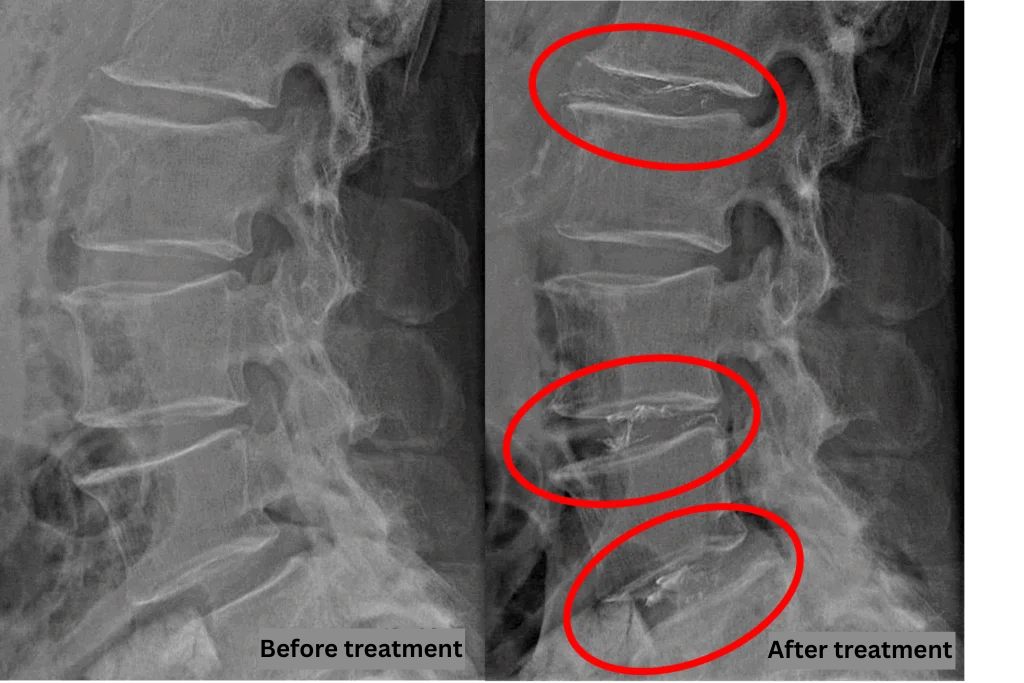

- L1/2, L3/4, L4/5: Disc Degeneration, Bulging, Foraminal Stenosis

- L2/3, L5/S: Disc Degeneration, Bulging

The above findings were also observed on the imaging.

These findings suggest that compression of the spinal canal at L1/2, L3/4, and L4/5 is the most likely cause of symptoms.

After consulting with the patient, the Cellgel Method was performed on L1/2, 3/4 and 4/5.

This is an image of the Discogel inserted into the intervertebral disc.